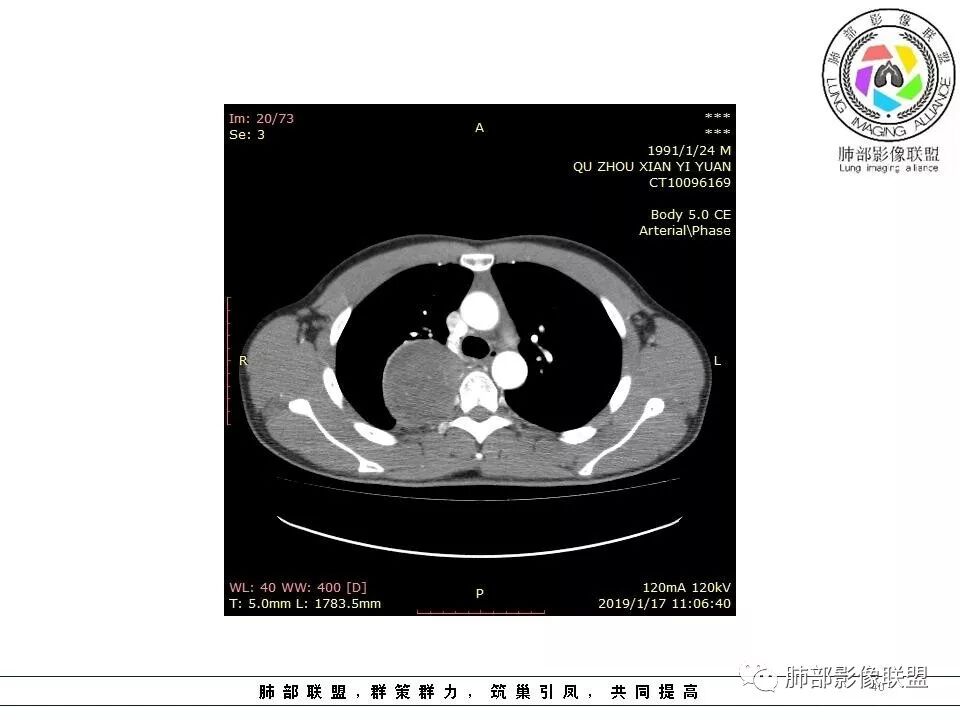

青年男性,间断胸痛;右侧脊柱旁可见一类圆形软组织密度影,密度欠均匀,增强扫描呈轻中度持续强化,邻近肺组织及肺动脉推移,可见肋间动脉供血,部分胸膜下脂肪可见,部分层面似见与右侧椎间孔相连。考虑后纵隔神经源性肿瘤。

青年男性,间断胸痛。右后纵膈脊柱旁软组织占位,形态规则类圆,边缘光整,肺组织受压,D字征,胸膜尾,肋间动脉供血。中度不均匀延迟强化。无支气管进入考虑来源于肺外、肿块与脊柱间未见明显脂肪间隙,考虑来源于胸膜外,考虑神经源性肿瘤,建议穿刺活检。

青年男性,右侧脊柱旁软组织肿块,边缘膨隆,密度不均,临近肺组织受压、胸膜增厚,增强后动脉期呈不均匀强化,并可见肋间动脉供血,延迟期强化较均匀,定位肺外,首先考虑SFT,神经源性肿瘤待排

右肺占位,跨越上叶后段、下叶背,边缘光滑,瘤肺界面清,见肺压缩缘(线样不张`强化),见胸膜尾征,胸膜下脂肪未见明显增厚,肋骨丶脊柱未见侵袭及受压,渐进性丶地图样强化,冠状位似见体循环供血

青年男性,右后上纵隔脊柱旁沟可见团状软组织影,边界清,密度尚均匀,推挤邻近肺组织,胸膜可见掀起,有肺动脉供血,增强轻度蛇皮样强化,纵隔淋巴结未见肿大,邻近骨质未见破坏,胸膜下脂肪间隙消失,考虑SFT孤立性纤维瘤可能性大,鉴别神经鞘瘤,节细胞瘤,建议活检。

青年男性,胸痛,右上纵膈脊柱旁肿块,形态光整规则,支气管被推移,临近的胸膜明显增厚,有胸膜掀起,增强后密度不均匀,可见蛇形血管征,血供似乎有两根血管供血,考虑SFT

1.右上胸内脊柱旁类圆形肿块,质地似乎比较坚实,密度稍显不均,但未显示明确的坏死。

如此密度形态的病灶位于肺边缘首先应当想到孤立性纤维瘤,可相邻胸膜未见明显的异常强化和胸膜方向延伸。

4.静脉期轻度不均匀强化,注意不是环形强化,亦未见明确的“AB区”,这点也不支持神经鞘瘤。临床及病灶轻度强化都不支持副节瘤。